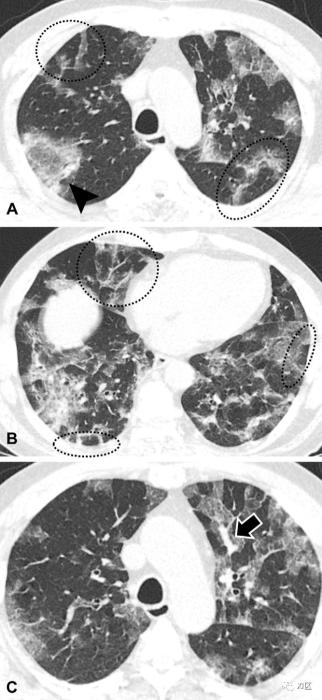

根据之前通过Hounsfield单位阈值或基于深度学习的方法使用自动肺血管分割的研究,新冠肺炎患者小于5 mm2(即BV5;对应于1.25 mm的直径)的血管中的肺血容量(BV)减少,而5–10 mm2(即BV5–10)和大于10 mm2(BV10)的血管体积增加(图8)。外周小血管的减少被认为是由病毒诱导的微循环破坏、血管收缩失调导致的血管阻力增加或微血栓或组织损伤导致的血管闭塞引起。就新冠肺炎患者的预后而言,BV5%(BV5占总BV的比例)是预测新冠肺炎患者不良结局(插管或死亡)的预后因素。在最近的一项研究中,奥密克戎变异株的BV5%高于德尔塔变异株,这表明奥密克戎变异株对肺血管的影响较小。虽然新冠肺炎患者的BV5下降幅度大于常规ARDS患者和健康人,但这并不是新冠肺炎的独有特征,在其他疾病中也可以观察到,包括流感肺炎、特发性肺纤维化、慢性阻塞性肺病和哮喘。与这一概念一致,新冠肺炎患者的舌下血管密度(sublingual vascular density,代表内脏微血管)显著降低了90%,而危重患者仅限于微毛细血管(直径4-6μm)。

图8:两名年龄相仿的老年患者的不同外周肺血管和病程。蓝色血管的横截面积为5mm2或更大,而黄色血管的横截面面积小于5mm2。(A,B)一名患有高血压的80岁男性的代表性三维图像显示,下叶为主的肺炎(红色;肺炎体积,3.9%)和肺血管中横截面积小于5 mm2的血容量(BV)相对于总肺BV的保留百分比(51.3%)。(C, D)一名患有高血压和糖尿病的 79 岁男性的代表性三维图像显示较大的下叶为主的肺炎(红色;肺炎体积,28.4%)和肺血管中横截面积小于5 mm2的血容量交叉- 相对于总肺 BV (31.8%)。后者死于新冠肺炎,而前者痊愈。血管树芽模式(Vascular Tree-in-Bud Pattern)